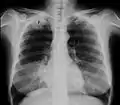

Pancoast-Tumor (P) im Röntgenbild der Lunge… -